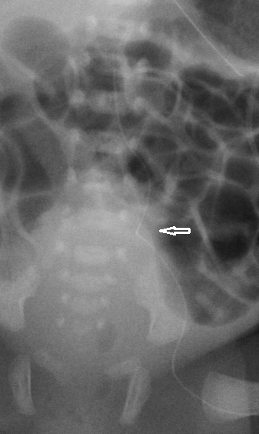

See illustrative x-rays below.

If there are any concerns that this complication has occurred, a lateral x-ray may show the line deviating posteriorly. If possible, seek advice from radiology about further imaging.

Such lines must not be used and the catheter should be removed. These lumbar veins are small, and extravasation of the infusate into the spinal canal may readily occur. This may result in permanent neurological injury and seizures.

These two x-rays show PICC lines that have entered the left lumbar vein. In both cases the line has not crossed the midline and lie to the left of the spine. Both X-rays show a kink in the route (arrow) although it is important to note that these kinks were not apparent on the initial x-rays and this feature cannot be relied upon |